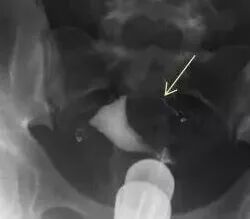

↓下图是输卵管积水的延迟片:

但是在以下情况中试管婴儿常常失败。这位女性因不孕症准备做试管婴儿,医生为她做了子宫输卵管造影,发现她的双侧输卵管远端非常扩张,这是什么问题?

原来这叫输卵管积水,慢性炎症是导致输卵管积水的原因。这种情况下,输卵管内的积水会流回宫腔,破坏宫腔怀孕的环境,试管婴儿失败!怎么办?